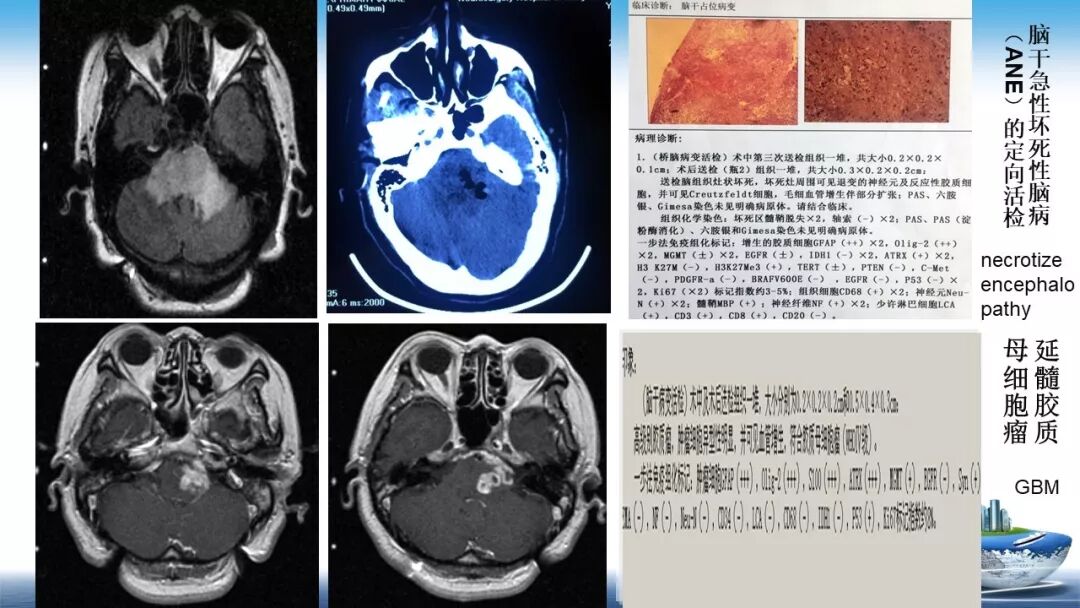

立体定向活检在脑干中线病变精准诊断中的作用

今天为大家带来的是中国人民解放军总医院第六医学中心(原中国人民解放军海军总医院)王亚明、于新、张剑宁带来的精彩课题分享:立体定向活检在脑干中线病变精准诊断中的作用,欢迎观看、阅读!